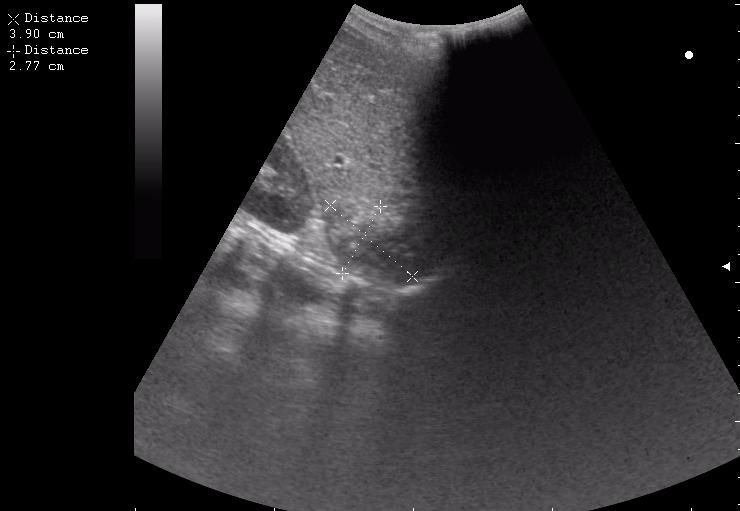

железный дрын вошел в правую подвздошную область, остановился в капсуле печени.

сегодня был селезёночный день.